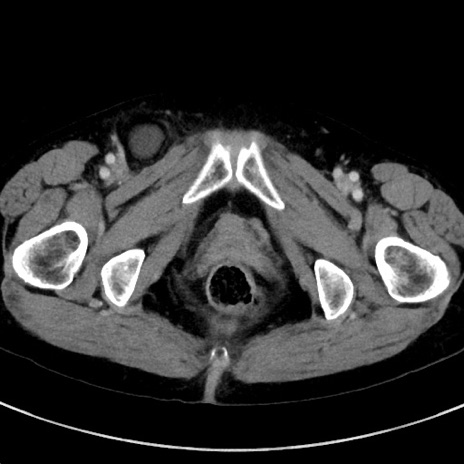

症例23(横断像)

【症例】70歳代女性

【主訴】下腹部痛・嘔吐

【現病歴】2日前より腹痛あり。昨日嘔吐あり。症状改善しないため来院。

【既往歴】胃GISTに対して胃部分切除後。

【身体所見】BT 37.1℃、BP 128/77mmHg、腹部:平坦・軟、下腹部に圧痛あり。

【データ】WBC 10200、CRP 0.31